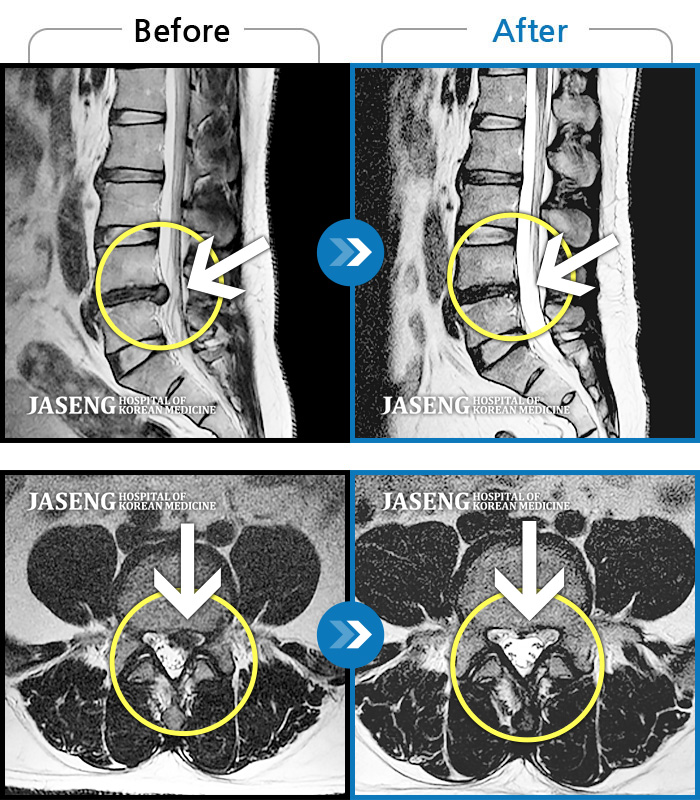

허리디스크

천안 · 윤영웅 원장

허리통증이 심해서 거동이 안돼요.

촬영시기

2021.09.13 ~ 2024.06.11

2024.06.21